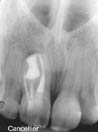

Preop

xray 16 year old white female presents from out of

state with buccal fistula between maxillary right

lateral #7 and central #8. Radiograph reveals

dens-in-dente at #8. Mesial part of #8 tests vital.

Tooth #7 tests vital. Gutta percha probe in fistula

points to #8.